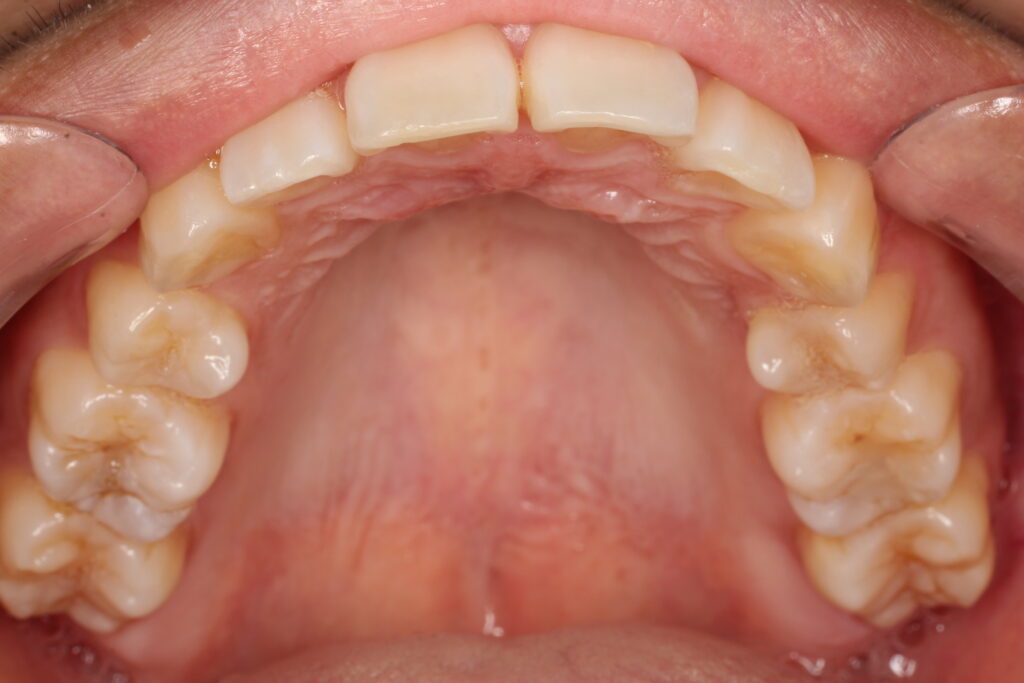

お口の中はとてもきれいな状態です。